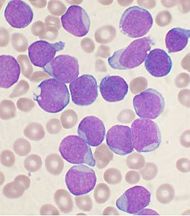

اللوكيميا

| اللوكـيميا | ||

| معدل الانتشار | 2.3 مليون (2015)[7] | |

| معدل البقاء 5 سنوات | 57% (الولايات المتحدة)[8] | |

| حالات الوفاة | 353.500 (2015)[6] | |

| عوامل الخطورة | شذوذات جينية معينة، منها متلازمة داون ومتلازمة بلوم وتوسع الشعريات الرنحي ataxia-telangiectasia والتعرض المفرط للإشعاع المؤيِّن وبعض المواد الكيميائية مثل البنزين benzene الموجود في الگازولين الخالي من الرصاص، والتعرض ڤيروس تي- الليمفاوي البشري. | |

| العلامات المنذرة | تعب، شحوب، فقدان وزن، إصابات مُعْدية متكررة، نزوف أنفية ونزوف أخرى، سهولة حدوث الرض. وقد تظهر هذه العلامات بصورة فجائية عند الأطفال. | |

| الكشف والتشخيص | الفحوص الدموية للكشف عن شذوذ خلايا الدم البيضاء، خزعة نقي العظم. | |

| العلاج | المعالجة الكيميائية هي الخط الأول للعلاج، وتستخدم الكثير من المشاركات الدوائية المضادة للسرطان بالتتابع، كما يتم نقل مركبات الدم والمضادات الحيوية (الصادات) للتقليل من خطر الإصابة بالعدوى (الخمج). وتستخدم المعالجة الشعاعية للجهاز العصبي المركزي في علاج الابيضاض اللمفاوي الحاد ALL، ويمكن أن تستخدم في أنواع أخرى أيضا. يمكن علاج الابيضاض النقوي المزمن بزرع نقي العظم إضافة إلى المعالجة الكيميائية. وقد أظهرت المعالجة بالإنترفيرون نتائج جيدة.

| |

| ملاحظات | على عكس الاعتقاد الشائع، فإن ابيضاض الدم يصيب البالغين أكثر بكثير من الأطفال، ويعتبر ابيضاض الدم اللمفاوي الحاد (ALL) الشكل الأكثر شيوعا عند الأطفال، في حين يعتبر ابيضاض الدم النقوي الحاد (AML) وابيضاض الدم اللمفاوي المزمن (CLL) الشكلين الأكثر شيوعا عند البالغين. | |